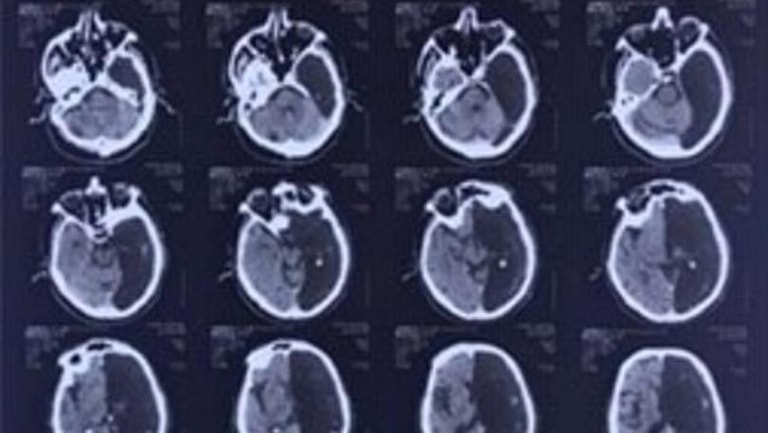

Medics in Moscow made the shocking discovery while running a CT scan when the man was admitted to hospital after a 'mini stroke'.

'Radiologists performed a computer tomography of his head and were puzzled for some time - the part of the brain of the retired man where the ischemia attack was supposed to have happened was not there at all.

'Instead of the left side of the brain there was a black "hole" in computer images.'

Specialists concluded that all his life the remaining right hemisphere of the brain had performed all the brain functions.